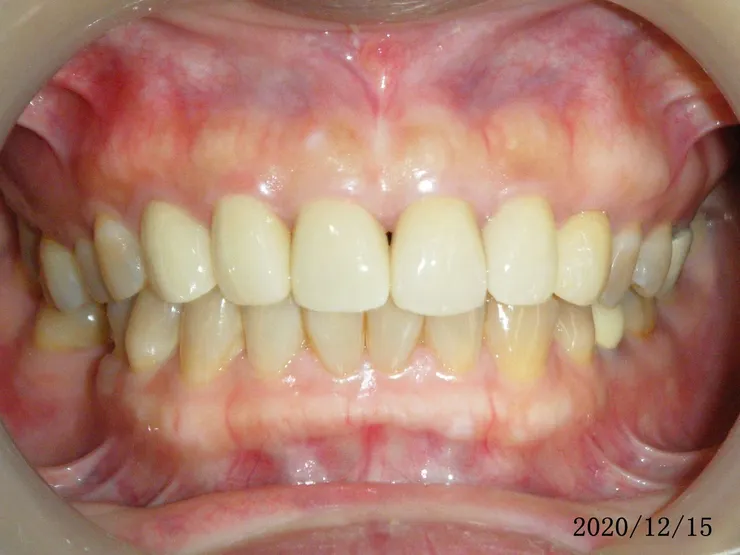

這是2021的,一樣自然好看

她有用音波牙刷潔牙,保持牙周健康,牙齦更飽滿了,假牙看起來更自然(可以跟她其他的金屬瓷牙比較)